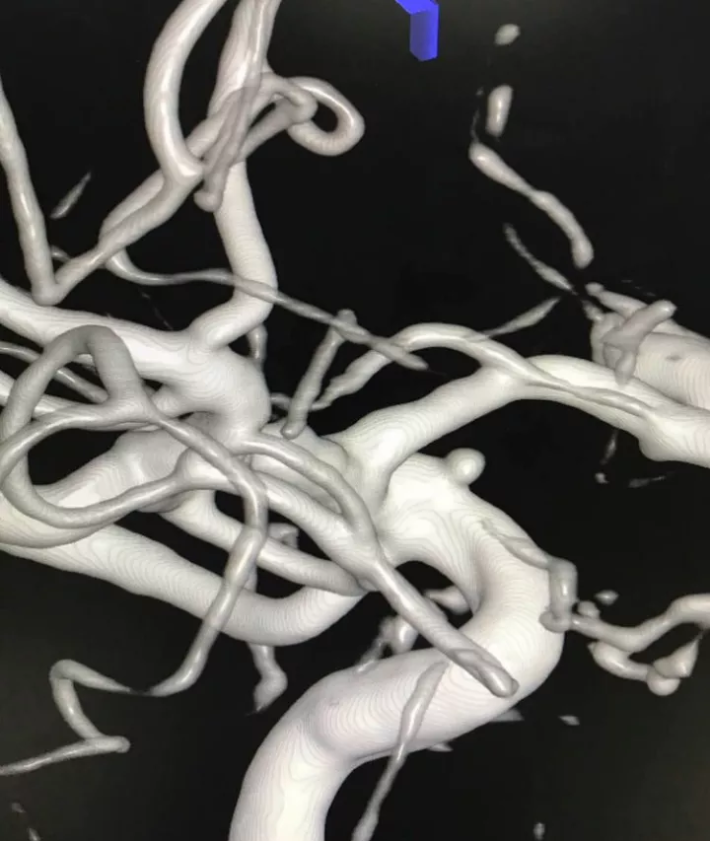

右颈内动脉造影三维重建显示C1段上壁微小动脉瘤

术后右颈内动脉造影三维重建,动脉瘤消失